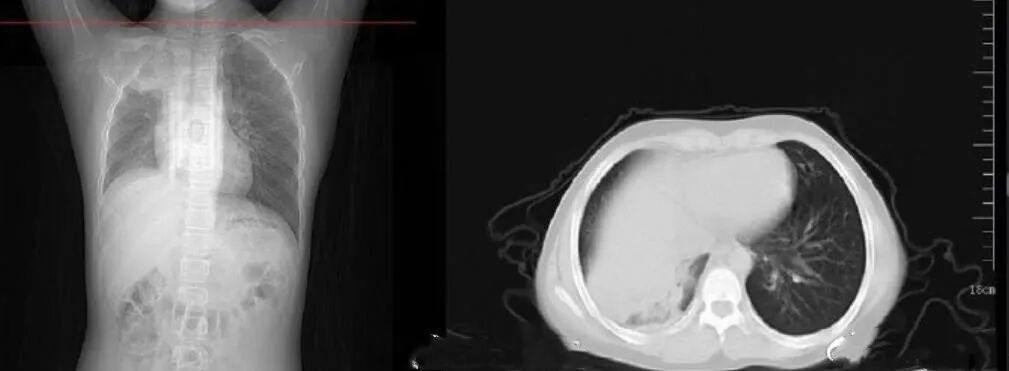

无独有偶,前不久,知名自媒体人樊登老师在全家感染后,自己也感染了。他发着烧给大家直播了4个小时,在视频中,他给大家提了一个醒,有种病叫做静默型低氧血症。

这种病没有明显症状(静默),但实际上血氧含量已经非常低。樊登说他的父亲就是感染后,患上了这个静默型低氧血症,家人赶紧把老人送到医院,结果拍CT一查,老人出现了大面积白肺。最终老人还是没有抢救过来图片

肺部是由肺泡组成的,肺泡里面充满空气,进行CT或者X线检查的时候,射线穿过肺泡,影像表现是黑色区域,但是当肺泡里出现炎症或感染,有渗出液和炎性细胞的时候,肺泡就被这些渗出液和炎性细胞所填充,射线就穿不透,在影像学上出现白色区域。

随着渗出液的吸收、炎症的消退,白肺的表现也会逐渐消退,肺部的影像学表现会逐步恢复为黑色区域。

并不是只要肺部出现了炎症就都叫白肺,一般来讲肺部炎症较重、渗出液较多,白色的影像区域面积达到70%—80%时,在临床上把它称为白肺。

出现白肺之后,患者就会出现低氧血症或者是呼吸窘迫。